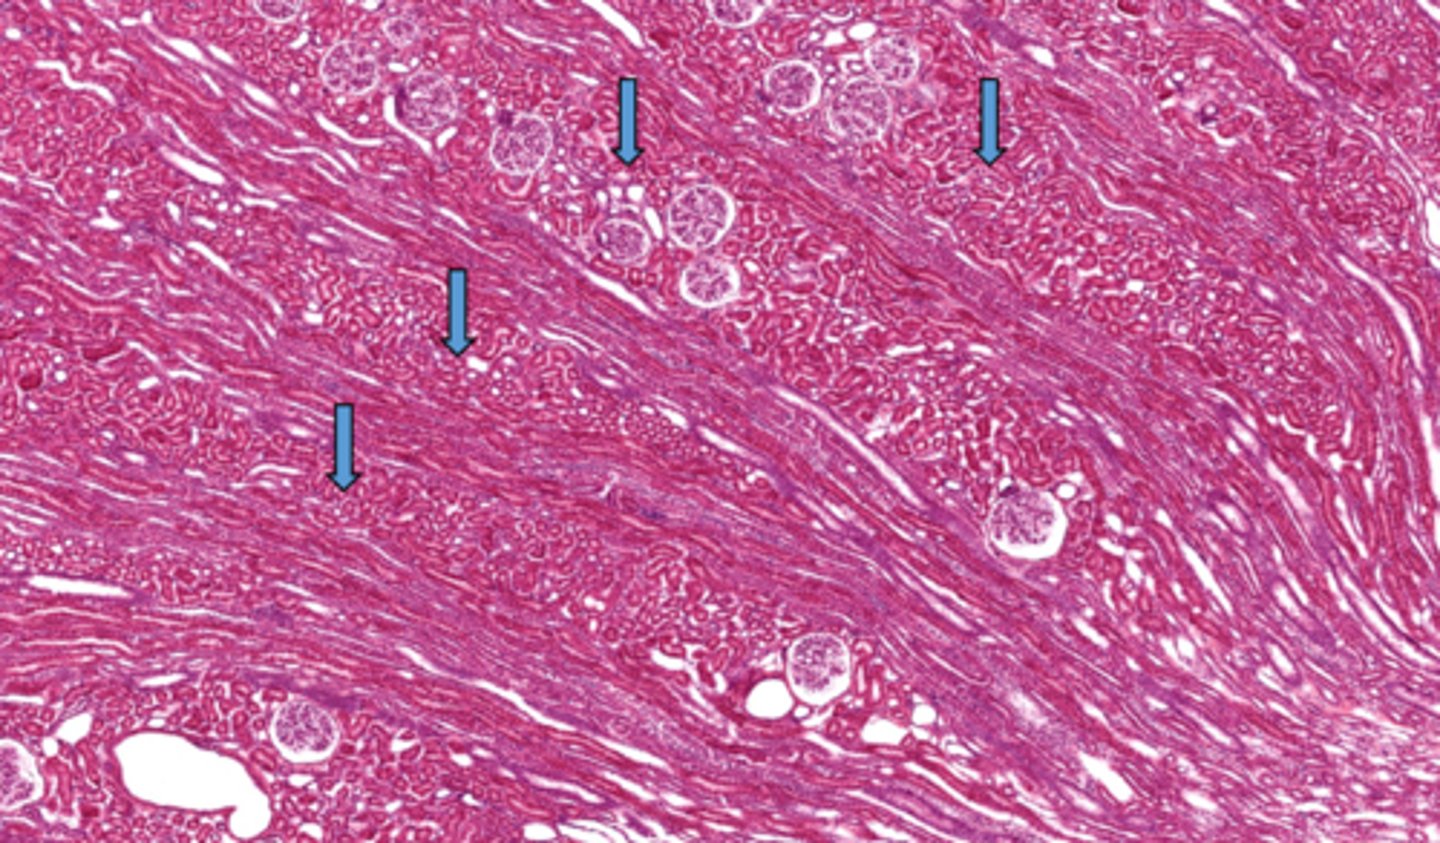

What division of blood vessels is found in the area outlined

arcuate vessels

Identify these collections of convoluted structures

cortical labyrinth (pars convoluta)

Identify the collection of straight structures in the cortex of the kidney

medullary rays